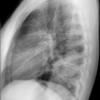

Case 3 RM & UL pneum Lat

Date: 07/04/2004

Views: 7249